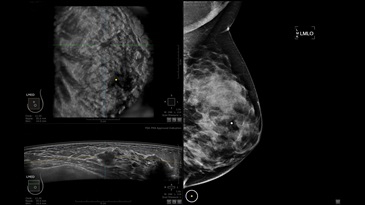

GE INVENIA ABUS – это современный УЗИ аппарат, который создан для точной и эффективной диагностики сканирования с высокой плотностью молочных желез. Выявляемость патологий раковых и предраковых стадий заболевания составляет 55%, что в конечном счете позволяет ставить врачу точные и своевременные диагнозы. Традиционные методы использования маммографии не показывают такой выявляемости, ограничиваясь лишь 3-38%.

УЗИ-аппарат GE INVENIA ABUS позволяет проводить максимально операторонезависимые процедуры, что значительно снижает риск неправильной постановки диагноза и сопутствующие издержки на обработку информации. Система готовит отчет в течение 3-х минут после сканирования, это безусловное преимущество по сравнению с обычным УЗИ сканером.

• датчик с изогнутой апертурой для качественного исследования

• сканирование одной грудной железы в трех проекциях не более 60 сек.;

• обработка результатов за три минуты.